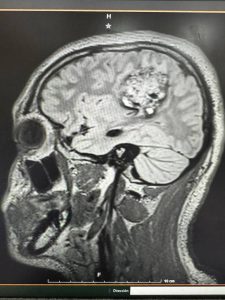

Un hecho sin precedentes ocurrió en Yucatán: especialistas del IMSS lograron realizar la primera craneotomía en un paciente pediátrico consciente. El joven de 16 años permaneció despierto mientras los médicos extirpaban un tumor cerebral de 5 centímetros, permitiendo monitorear en tiempo real su lenguaje, movilidad y funciones cognitivas.

Este tipo de intervención —conocida como craneotomía con paciente despierto— es una técnica avanzada que permite evaluar las áreas del cerebro en tiempo real, reduciendo el riesgo de dañar zonas esenciales. Su aplicación en un adolescente es un paso histórico que coloca a Yucatán en el mapa de la medicina moderna.

Durante las seis horas que duró la operación, el equipo médico mantuvo una comunicación constante con el paciente, quien respondía preguntas, movía las extremidades y repetía palabras para garantizar que las áreas del habla y la motricidad permanecieran intactas.

Tras seis horas de intervención, el tumor fue retirado exitosamente al 100% y el paciente preservó sus funciones motrices y del habla, marcando un hito histórico en la medicina de Yucatán y del país.